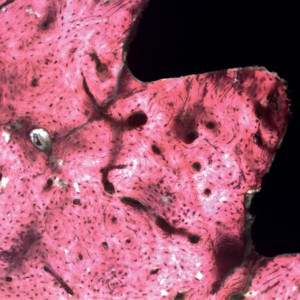

BIC% was higher in the T group (64.8 ± 7.4%; median of 66.0) after four weeks than in the C group (50.4 ± 7.9%; median of 49.5). These data and statistical significance (p = 0.0005) are shown in Figure 6. The new bone formed around the implants in the C group was not completely mineralized (Fig. 7). In the T group, however, better organization and mineralization were found after four weeks (Fig. 8) and there was better stimulation of the medullary bone portion (Fig. 9).

fig. 8a

fig. 8b

Fig. 8a & 8b Histological images showing bone maturation and mineralization in the T group after four weeks, with more advanced new bone formation around the implants in the new bone organization areas. (a) 100× and (b) 400× magnification. Staining with picro-sirius-hematoxylin.

fig. 9 Histological images showing bone maturation and the BIC after four weeks. There was visibly better stimulation of the medullary bone portion in the T group in comparison to the C group (yellow arrows).